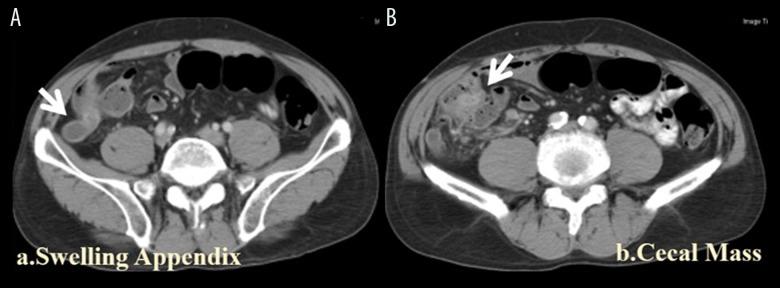

BACKGROUND Minimally invasive surgery (MIS) has rapidly advanced, but its use in transplant patients has lagged. We share our experience of MIS for patients after kidney and liver transplantation and compare our results with similar studies in the literature. MATERIAL AND METHODS This study included 14 MIS (12 laparoscopic, 2 transvaginal) procedures for 13 transplant cases (6 liver and 7 kidney) done from May 2006 to May 2018. Gastrointestinal surgery was performed in 6 cases: appendectomy performed 8 months after liver transplant and 16 months after kidney transplant in 2 cases, radical right hemi-colectomy performed 6 weeks after liver transplant in 1 case; exploration for chylous ascites 6 months after liver transplant in 1 case, sleeve gastrectomy performed 3 years after kidney transplant in 1 case, and partial hepatectomy performed 12 years after kidney transplant in 1 case. For urological problems, 2 patients received ipsilateral right-side nephroureterectomy performed 10 and 12 years after kidney transplant, and 1 patient received contralateral left-side nephroureterectomy performed 12 years after kidney transplant. The 2 liver transplant patients with huge incisional hernias received repair approximately 3 and 2 years after liver transplant. Three patients underwent gynecological surgery: 2 transvaginal for pelvic floor reconstruction in 1 patient with liver transplant and 1 hysterectomy in a kidney transplant patient, and 1 laparoscopic-assisted hysterectomy in a kidney transplant patient. We retrospectively analyzed the clinical presentation, operative findings, operation time, postoperative complications, and length of stay. RESULTS The postoperative course was uneventful, with early resumption of oral intake, including immunosuppressants administered the same as in the non-transplant patients. All surgical procedures in these transplant patients were achieved without conversion, showed stable kidney and liver function, had better surgical outcomes in comparison with traditional surgery, and most of them were discharged within 1 week. CONCLUSIONS Laparoscopic and non-laparoscopic MIS surgery are feasible and safe for abdominal organ transplant patients and are helpful for timely intervention in cases with acute abdomen. No adjustment of immunosuppressant is usually needed, as oral intake can be resumed very soon after surgery.

这项研究包括了 14 例 MIS(12 例腹腔镜,2 例经阴道)手术,涉及 13 例移植病例(6 例肝移植,7 例肾移植),手术时间为 2006 年 5 月至 2018 年 5 月。胃肠道手术 6 例:2 例肝移植后 8 个月和 16 个月行阑尾切除术,1 例肝移植后 6 周行根治性右半结肠切除术;1 例肝移植后 6 个月因乳糜性腹水行探查术,1 例肾移植后 3 年行袖状胃切除术,1 例肾移植后 12 年行部分肝切除术。对于泌尿外科问题,2 例患者接受了同侧右侧肾输尿管切除术,分别在肾移植后 10 年和 12 年进行,1 例患者接受了对侧左侧肾输尿管切除术,在肾移植后 12 年进行。2 例肝移植后巨大切口疝的患者在肝移植后约 3 年和 2 年接受了修复。3 例患者接受了妇科手术:2 例经阴道用于肝移植患者的盆底重建,1 例肾移植患者行子宫切除术,1 例肾移植患者行腹腔镜辅助子宫切除术。我们回顾性分析了临床症状、手术发现、手术时间、术后并发症和住院时间。